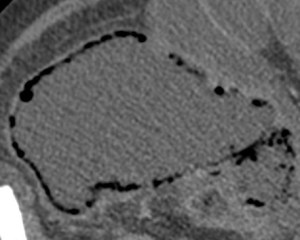

Se realiza TC de abdomen en vacío y con contraste en fase portal:

Estamos ante un cuadro de isquemia intestinal en un paciente con bajo gasto cardiaco con afectación principal de asas intestino delgado, territorio vacularizado por la arteria mesentérica superior.

La neumatosis intestinal consiste en aire localizado en la pared del intestino. Se produce por discontinuidad de la pared con paso de aire hacia las capas más externas y a las venas intramurales.

La presencia de neumatosis portal y mesentérica consiste en pequeñas burbujas de gas dentro de los vasos mesentéricos o que también pueden extenderse hacia las ramas intrahepáticas de la vena porta, encontrándose típicamente en la periferia del hígado.